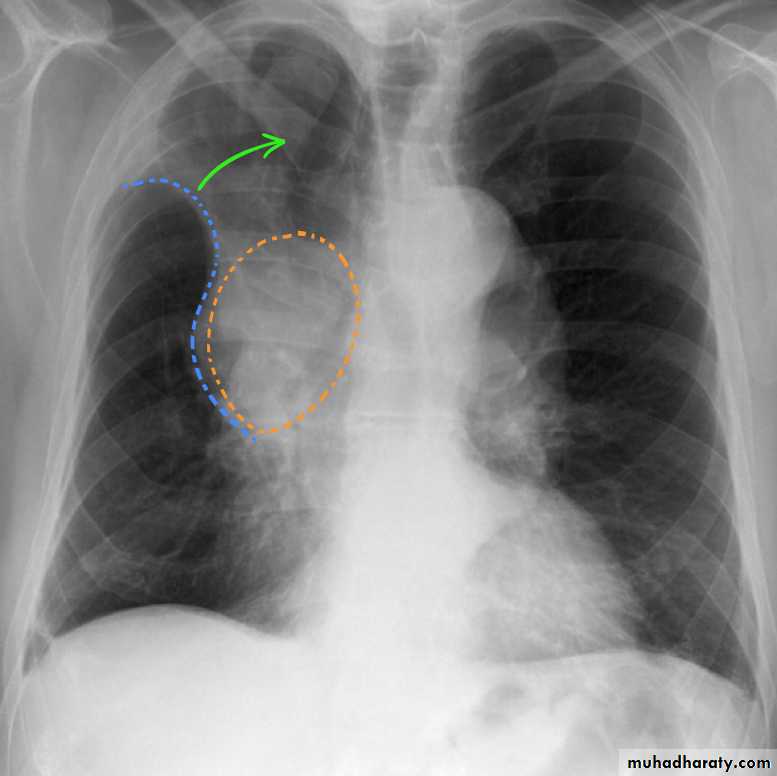

A common cause of lobar collapse is a hilar mass. When a right hilar mass is combined with collapse of the right upper lobe, the result is an S shape to elevated horizontal fissure. This is known as Golden S sign .

Radiology of BGCA

The appearance depends on the location of the lesion.1.The more central lesions may merely appear as a bulky hilum, representing the tumor and local nodal involvement the lesion is irregular in outline have spiky or sun ray spiculation .

2.Lobar collapse may be seen due to obstruction of a bronchus. When the right upper lobe is collapsed and a hilar mass is present, this is known as the Golden S sign.

3.A more peripheral location may appear as a rounded or spiculated mass. Cavitation may be seen as an air-fluid level , more to be large cell CA .